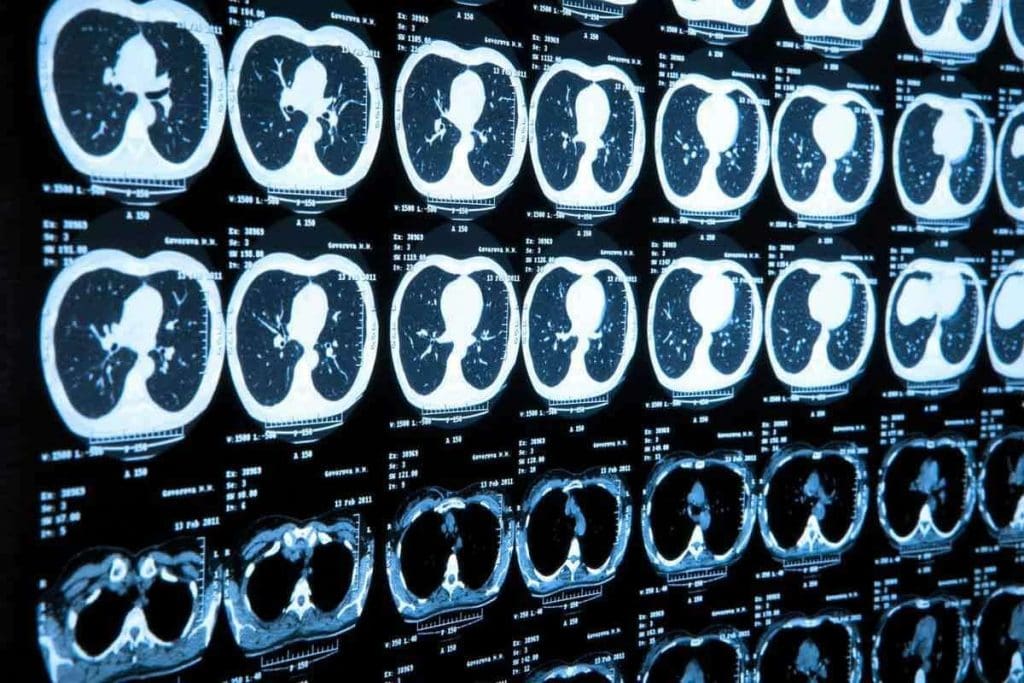

Image Resolution and Detail: What Each Scan Reveals

PET CT and MRI scans have different strengths in image quality and detail. They meet different needs in medical imaging. This makes them great together in helping patients.

Functional and Metabolic Information

PET CT scans are top-notch for functional and metabolic information. They use special tracers to show how tissues work. This is key in finding and understanding cancer.

By combining PET and CT, doctors get both how tissues work and their structure in one scan. This makes diagnosis more accurate.

Anatomical Precision and Soft Tissue Contrast

MRI scans are known for their anatomical precision and soft tissue contrast. They use magnetic fields and radio waves to show soft tissues clearly. This is super helpful for the brain, spine, and joints.

MRI’s high-quality images help doctors see tissue structure and find small problems. These might not show up on other scans.